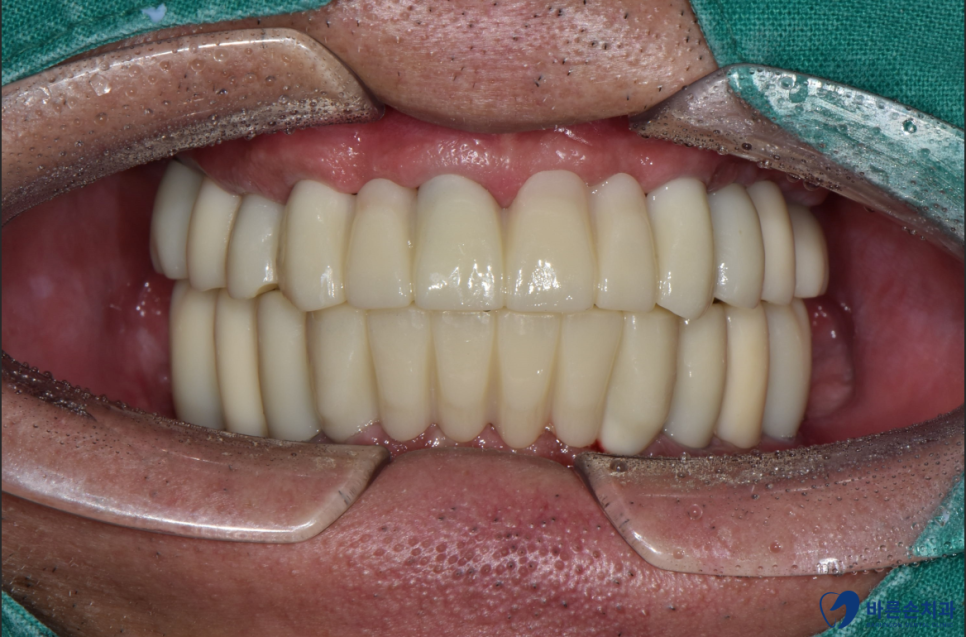

치아가 전부 없는 상태에서, 처음부터 교합을 맞춰야 하기 때문에

임시치아 상태로 2~3 개월 사용하시다가

안정적으로 되고 나서 최종 지르코니아 보철물로 교체합니다.

이렇게 전체 임플란트 치료가 마무리되었습니다~

식사 시 편안함은 물론이고,

심미적으로도 치아가 없을 때와 인상이 많이 달라지기 때문에,

사회 생활도 달라지신다고 하십니다.